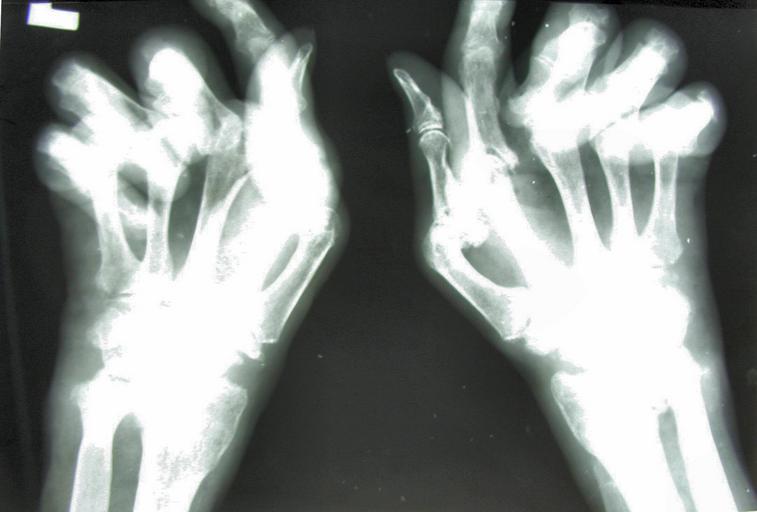

MAKE A MEME View Large Image Reumatoidalne zapalenie stawow 01.jpg Reumatoidalne zapalenie stawów - obraz RTG dłoni - duże zmiany destrukcyjne stawów przykurcze deformacje skostnienia Rheumatoid arthritis - X-ray image of the hand - large changes in destructive ...

Keywords: Reumatoidalne zapalenie stawow 01.jpg Reumatoidalne zapalenie stawów - obraz RTG dłoni - duże zmiany destrukcyjne stawów przykurcze deformacje skostnienia Rheumatoid arthritis - X-ray image of the hand - large changes in destructive arthritis contractures deformity ossification Arthritis mutilans pl wikipedia Masur CommonsHelper 2005-06-27 Jojo wikipedia pl Jojo original upload log page pl wikipedia Rzs_01 jpg 2005-06-27 10 32 Jojo 2162×1463× 312874 bytes <nowiki>Reumatoidalne zapalenie stawów - obraz RTG dłoni - duże zmiany destrukcyjne stawów przykurcze deformacje skostnienia Jestem autorem tego zdjęcia i nadaje mu status PD PD </nowiki> Rheumatoid arthritis Hands Ossification